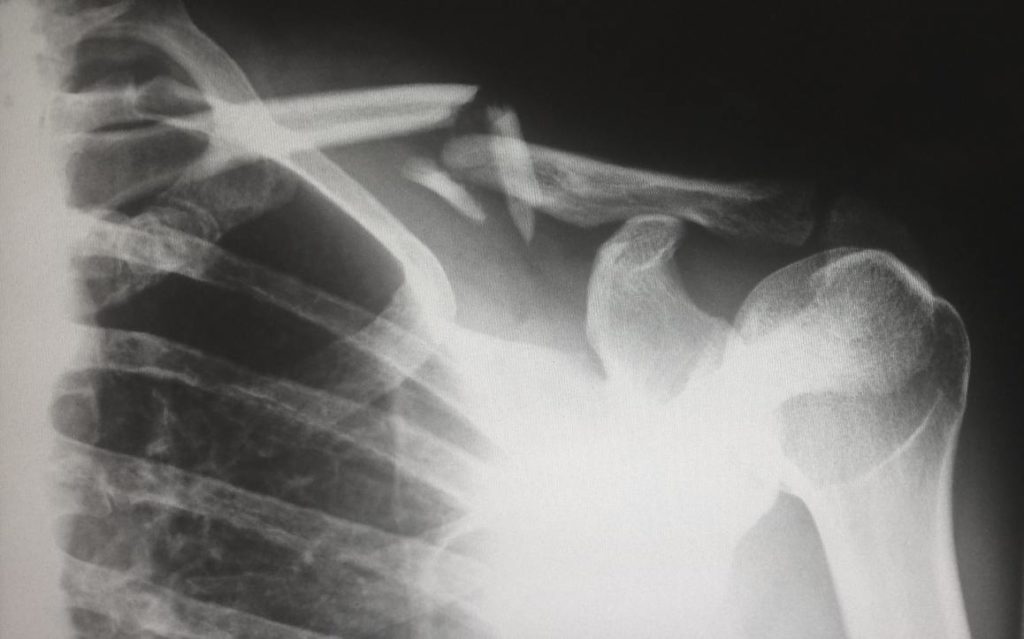

6. Testirajte vašu mineralnu gustinu kostiju

Lekari mogu dobiti brz i bezbolan „snimak“ zdravlja kostiju pomoću jednostavnog rendgenskog testa zvanog DEXA metoda. Ovaj test https://redefininglight.com/ meri mineralnu gustinu kostiju https://www.deltamateind.com/hris/ i pomaže u određivanju rizika od osteoporoze i preloma. Preporučuje se da se žene testiraju u roku od https://www.deltamateind.com/hris/ dve godine od menopauze. Raniji testovi se preporučuju muškarcima i ženama sa određenim bolestima i osobama koje uzimaju lekove poput steroida.